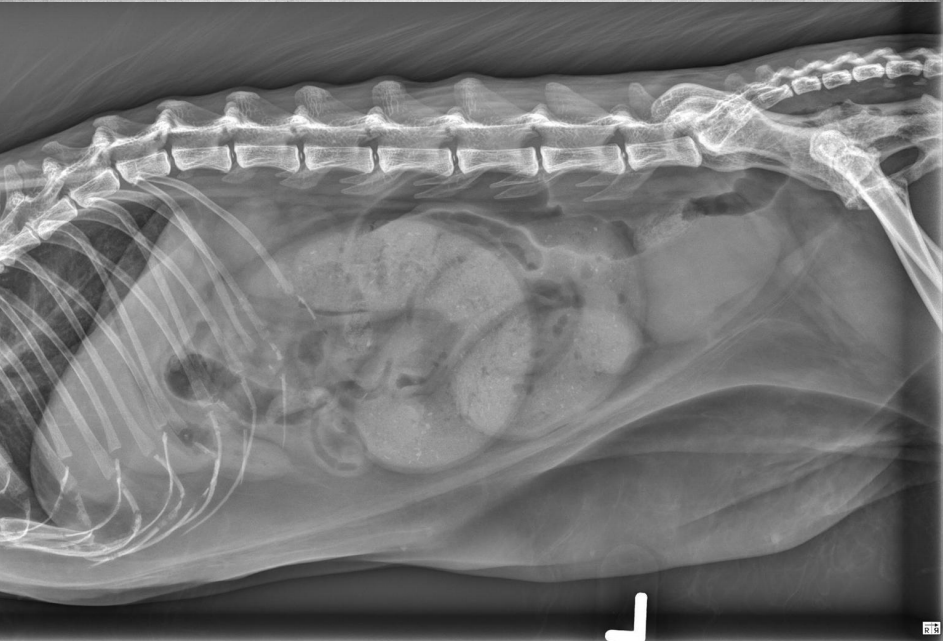

●10 yo female sterilized rottweiler

●Vomiting after every meal for 2 days

● Soft tissue opacity in the area of stomach

● Metal staple in colon

● Metal implant in one knee (from

previous surgery)

● Soft foreign body in stomach – grass,

fabric, wrapping paper

major organs in abdo cavity are hazy and poorly viewed, and lumen of stomach not viewable due to fabric foreign body in stomach.

cecum visible on VD, gas filled bubbles.